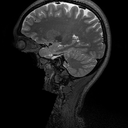

The main consequence of this result is that there is an accuracy-hallucination barrier. If the map performs too well on a certain image with detail lying close to , then it will hallucinate, by incorrectly transferring this detail to another image . Note this situation can arise even when : if is ill-conditioned then there exist many ‘candidate’ details for which is small while is not. In Fig. 2 we demonstrate an example of this effect. A NN is trained to accurately recover a brain image with artificial details. Then when used to reconstruct the detail-free brain image, it hallucinates one of the details. Theorem 4.1 also explains why only one of the details is transferred in this case, and not the other.

Fig. 2 presents an example of this result. In this figure, the ‘Mickey Mouse’ detail , whereas the ‘Thumb’ detail has relatively large measurements, i.e., . The NN is trained to recover the image . As a result, it incorrectly transfers the detail , while the detail is handled correctly (i.e., it is not transferred). Fig. 4 shows another example of this effect. In this case, is a subsampled Radon transform, which models a CT imaging scenario. Here, the NN is trained to recover the detail image , and as a result, it incorrectly transfer the detail when recovering the detail-free image .

In Fig. 2, we trained a NN to reconstruct the image , along with 1200 other images from the fastMRI brain dataset. Here is the brain image seen in the figure, is the thumb detail and is the Mickey Mouse detail. The sampling operator used in the experiment was a subsampled two-dimensional Fourier transform with . The sampling pattern is shown in Fig. 7. The Mickey Mouse detail was designed so that .

The ground truth images in the fastMRI dataset consist of magnitude images of size . In our experiments, we resized these images to pixels and stored them as real-valued images with pixel values in the interval . The detail is complex-valued, so any image with this detail is necessarily stored as a complex-valued image. To create the input data for the NN, we synthetically sampled these images with the sampling operator described above.

The NN used a U-net combined with the adjoint of the sampling operator. The NN was trained in two phases. First, we trained the NN for 500 epochs with random Gaussian noise added to the measurements. Then we ran a fine-tuning phase for 100 epochs with noiseless measurements. We used the Adam optimizer with a gradually decaying learning rate (see the GitHub page for details) and a mean-squared-error loss function.

The image was part of the training set, whereas the images and were not. In Fig. 2 we have cropped the images to pixels to remove some dark areas surrounding the brain.